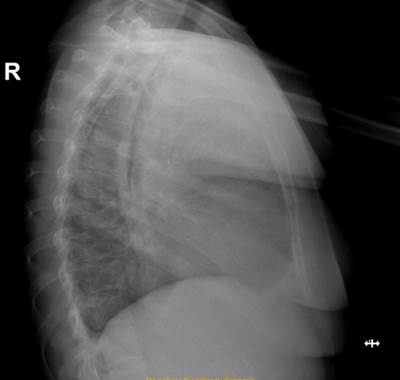

Figura 3:  Radiografía de tórax LAT.

Imagen tomada de: Caso Clínico Clínica Abendaño.  Loja - Ecuador